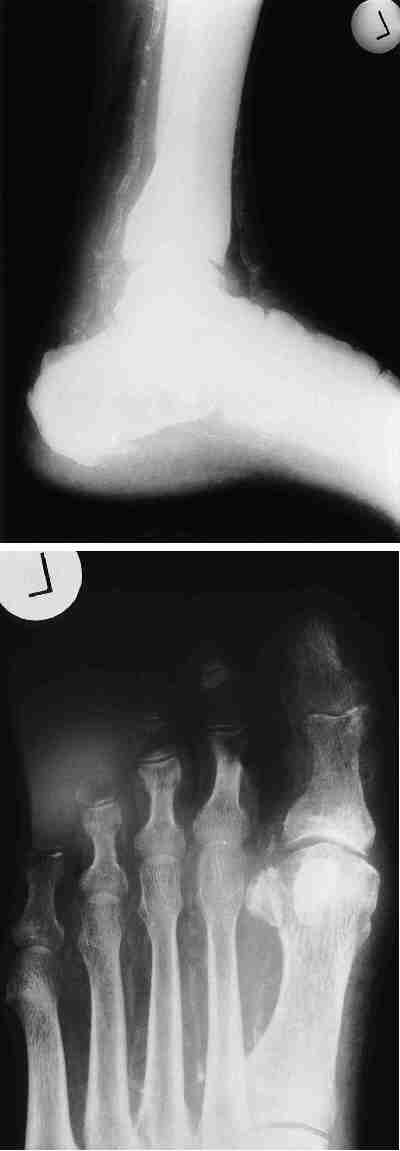

Diabetischer Fuß: Bildteil - Mediasklerose

Abb. 2:Nativ-Darstellung der Interdigitalarterien bei Mediasklerose (Mönckeberg-Sklerose) bei langjährigem Diabetes mellitus.